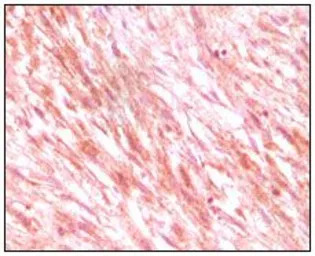

IHC-P analysis of maligant mesenchymoma tissue using GTX83074 c-Kit antibody [8D7].